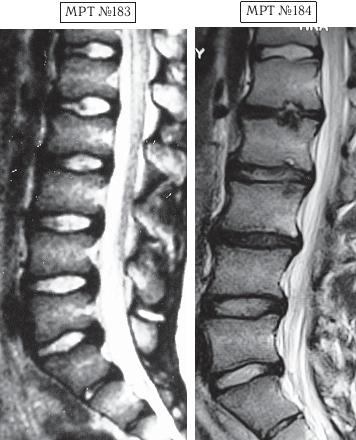

МРТ № 4

МРТ № 5

На МРТ № 4 наблюдается межпозвонковый диск в начальной стадии развития дегенеративно-дистрофического процесса.

На МРТ № 5 наблюдается межпозвонковый диск на более поздней стадии развития дегенеративно-дистрофического процесса.